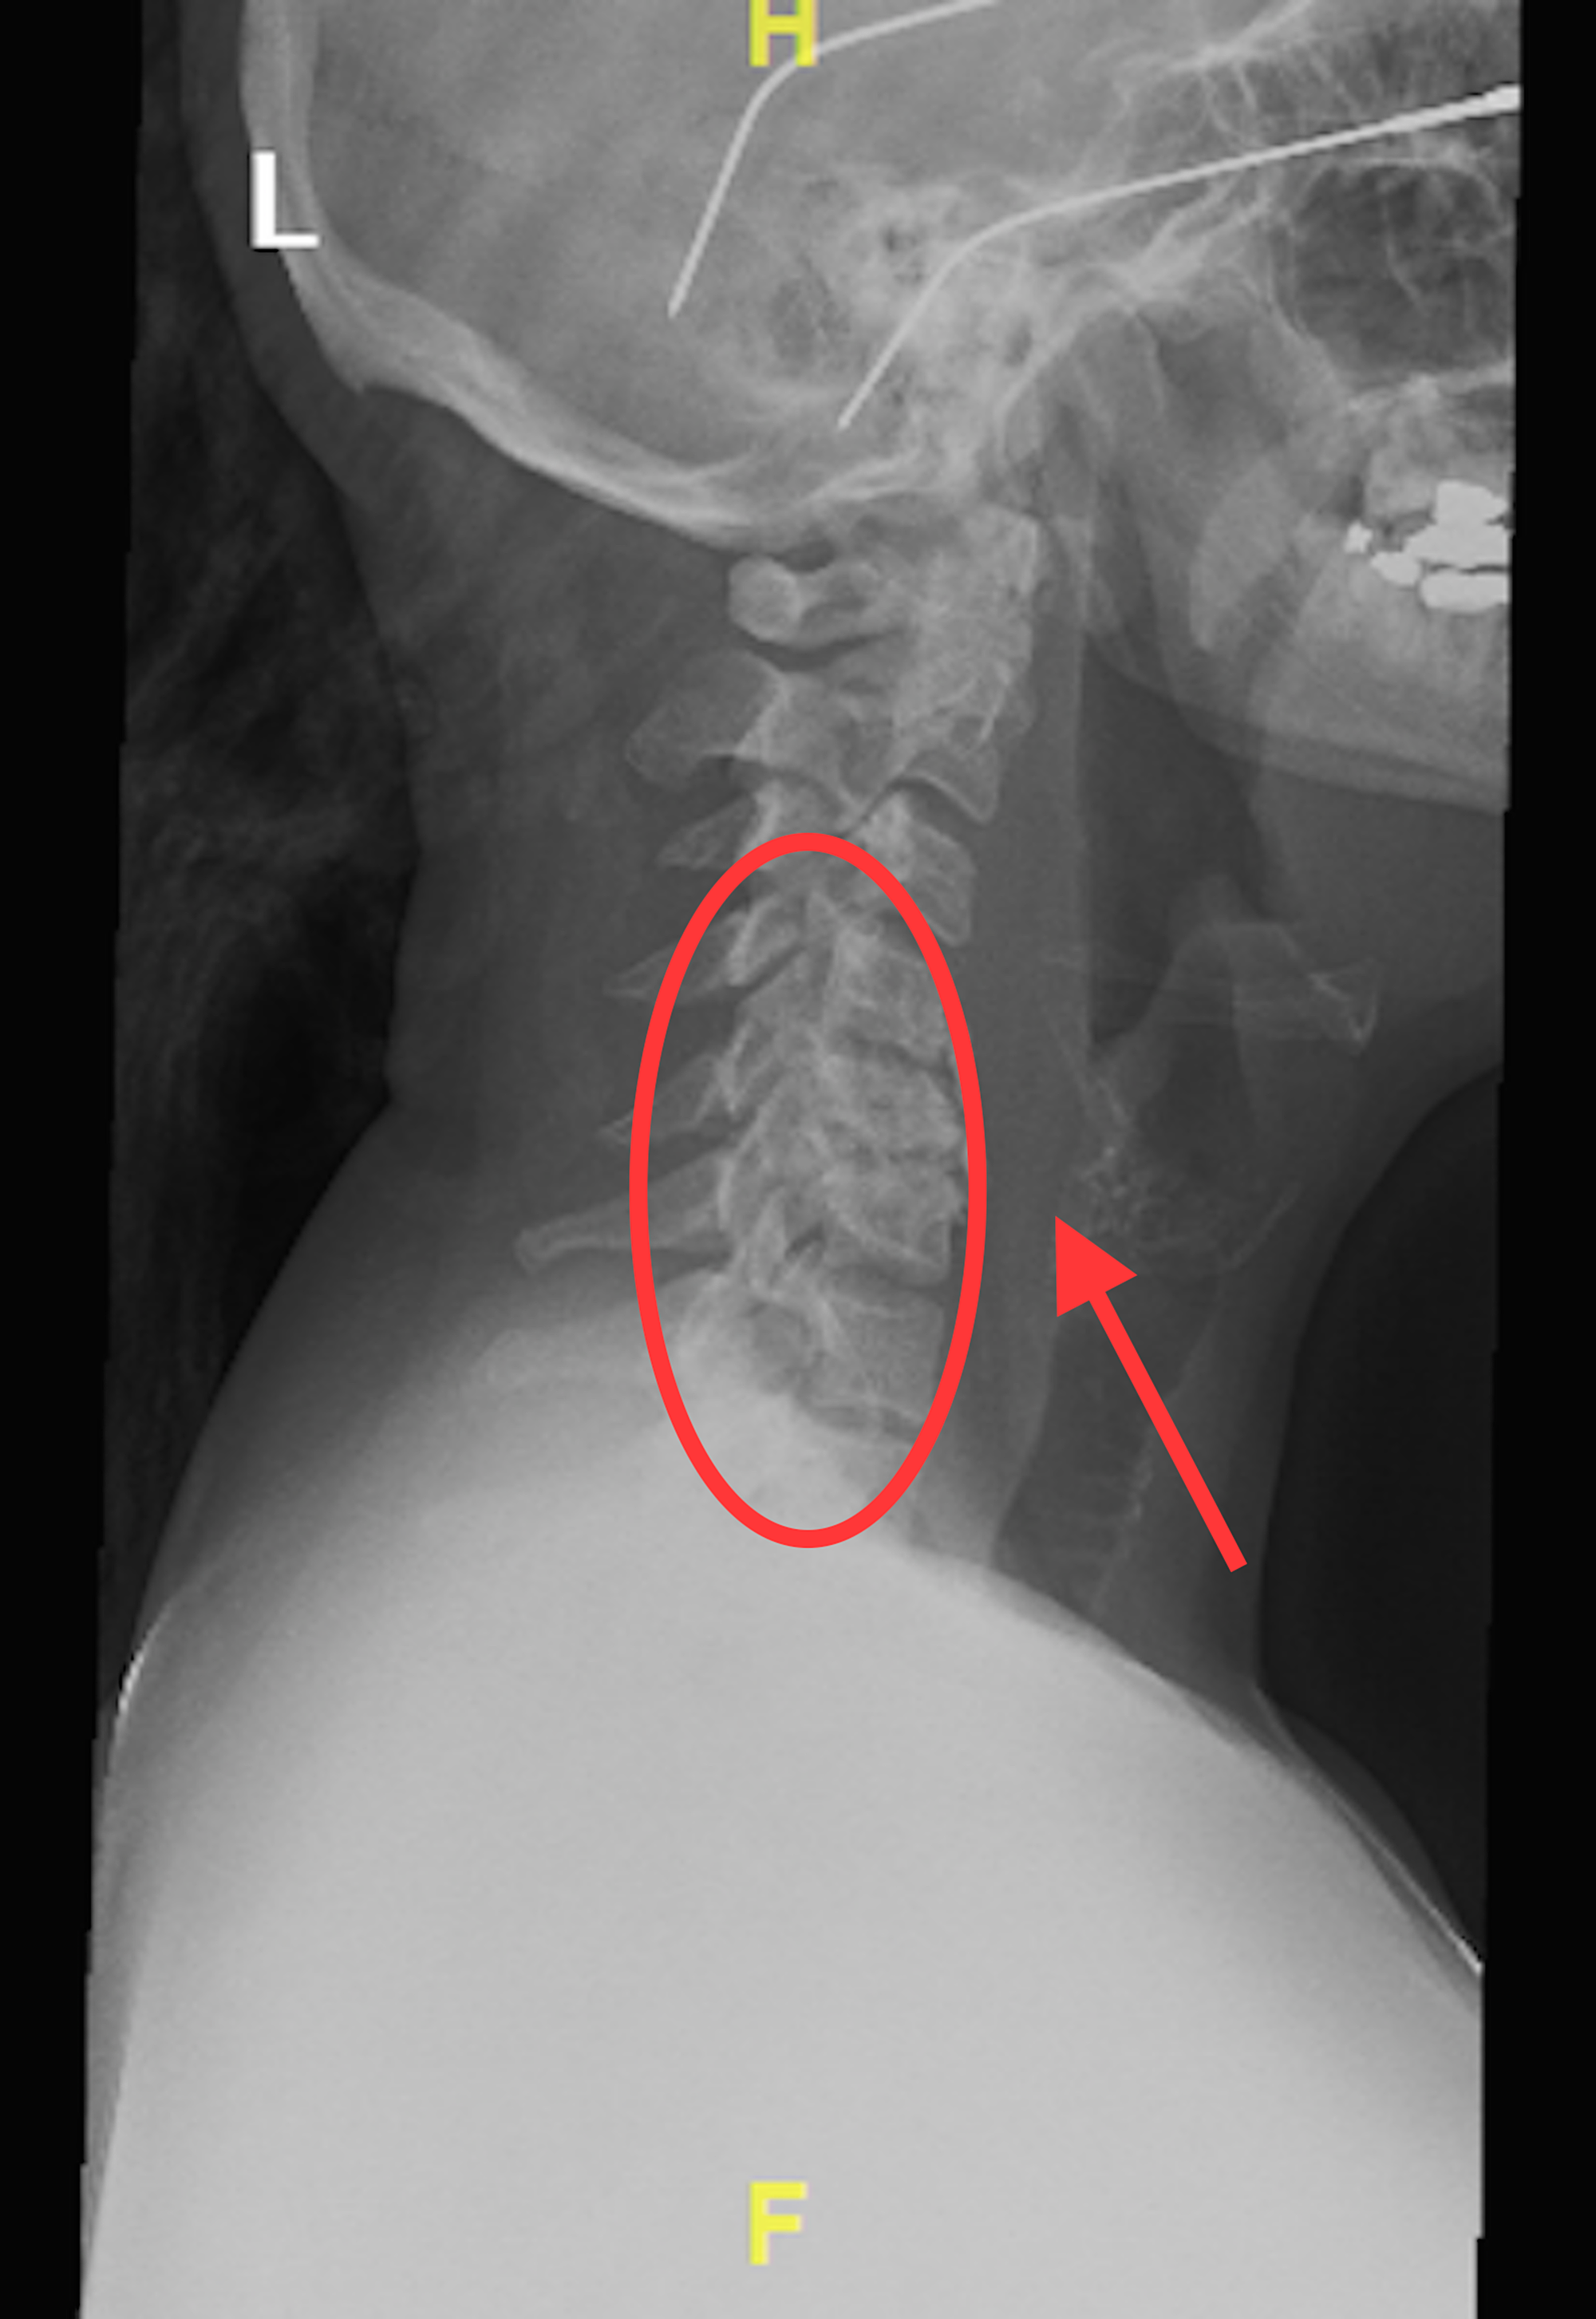

From www.cureus.com

Cureus Acute Calcific Tendonitis of the Longus Colli An What Causes Calcium Deposits All Over Body Calcification occurs when calcium builds up in areas of body tissue where calcium normally doesn’t exist. Coronary artery calcification is a collection of calcium in your heart’s two main arteries, also called your coronary arteries. We’ll tell you how to get rid of calcium deposits, based. Over time, the calcium deposits combine to form “speckles” or spots that can later. What Causes Calcium Deposits All Over Body.